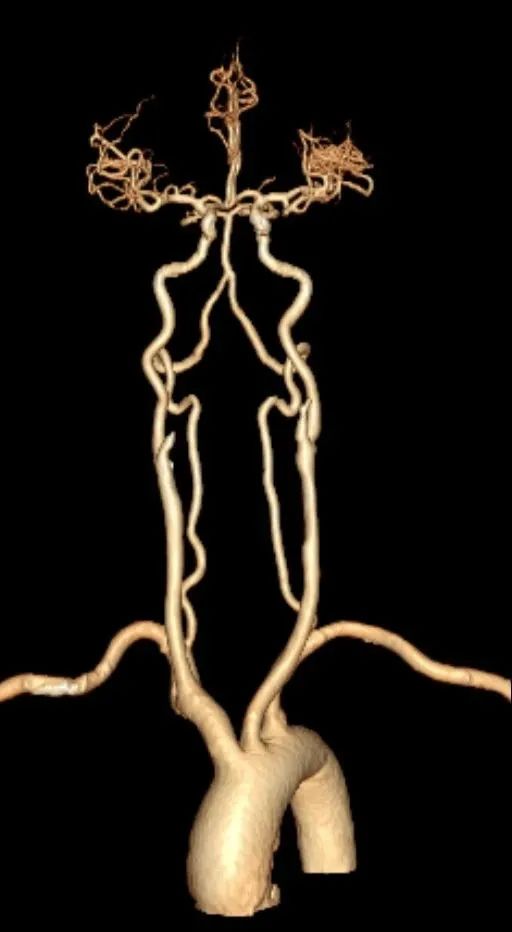

CT 血管造影(CTA),即 CT 血管成像,是一种利用计算机三维重建方法合成的非创伤性血管成像技术,可以在没有创伤的情况下,很好地了解身体中血管的情况。具有时间短、无创、特异性和敏感性高,时间和空间分辨率高等特点,能全方位显示出血管病灶,对于经其他检查已经明确患有血管疾病,需进一步了解病情严重程度具有重要的意义。

通过 CT 血管成像,可显示动脉病变,如血管闭塞、动脉瘤及夹层动脉瘤、血管畸形、血管损伤、心脏冠状动脉病变等。可进行冠心病 CT 筛查,冠心病术前、术后评估,脑卒中一站式检查,灌注成像等。

CT 血管造影(CTA)检查适用于动脉夹层、动脉瘤、不明原因出血、缺血性疾病、血管畸形、动脉栓塞、动脉硬化、动脉变异等血管疾病。

CTA 检查在大血管、外周血管疾病、心脏冠状动脉相关疾病、中枢神经系统疾病以及肿瘤疾病的诊断中发挥着重要作用。